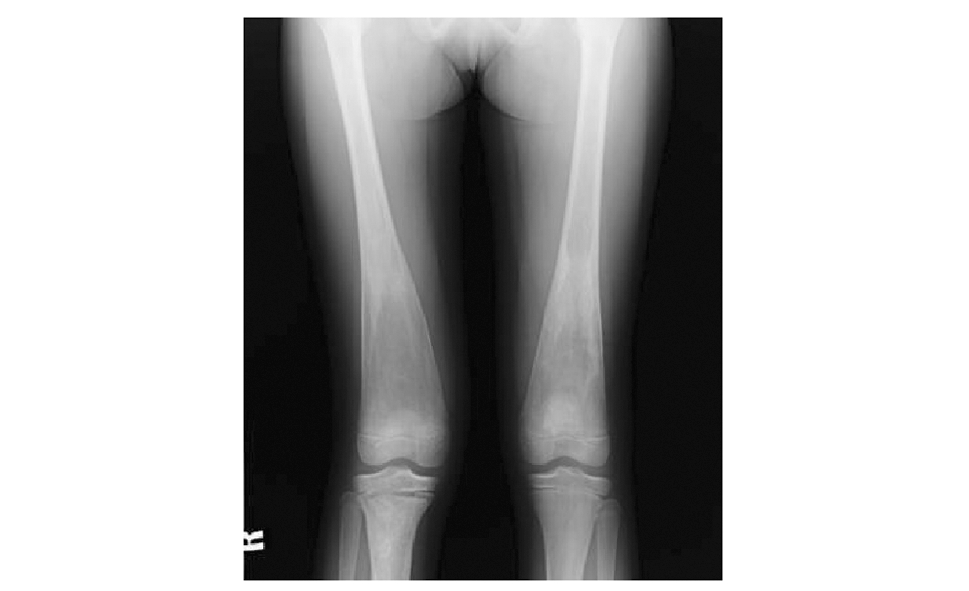

主要用于对骨骼系统的评估,GD的典型征象是弥漫性骨质疏松和股骨远端膨大呈“锥形瓶样”改变(图2),受累骨质包括长骨、椎体、肋骨及手足骨。可发生病理性骨折、蜂窝状或粗大的溶骨性骨质破坏、骨梗死以及继发的修复性骨膜反应和骨质硬化性改变。

图 2 1例女性戈谢病患者,12岁,双侧股骨X线示骨质密度减低,远端膨大呈典型的“锥形瓶样”改变